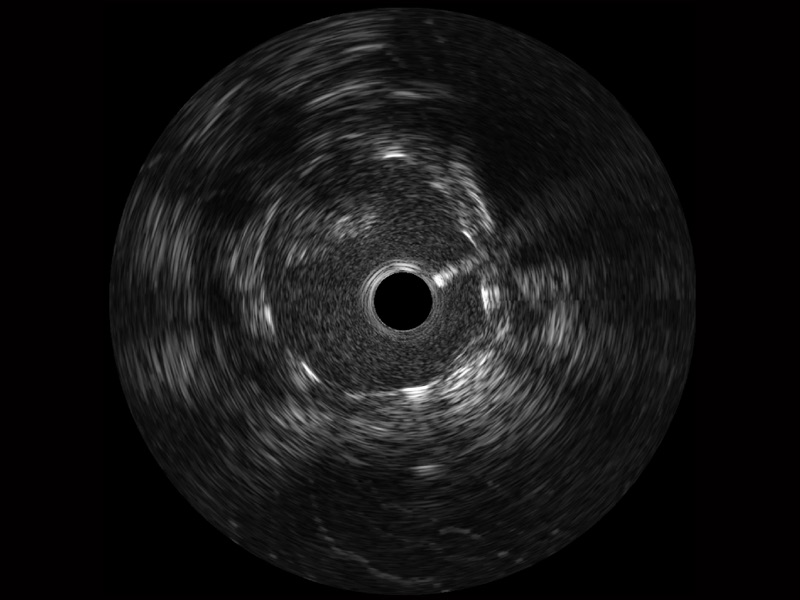

• MILE米乐集团官网宽频IVUS图像

对比传统IVUS导管成像,MILE米乐集团官网宽频IVUS图像的近场支架梁显影更细腻,远场中膜外血管仍清晰可辨,兼顾远中近,兼顾分辨力与穿透深度